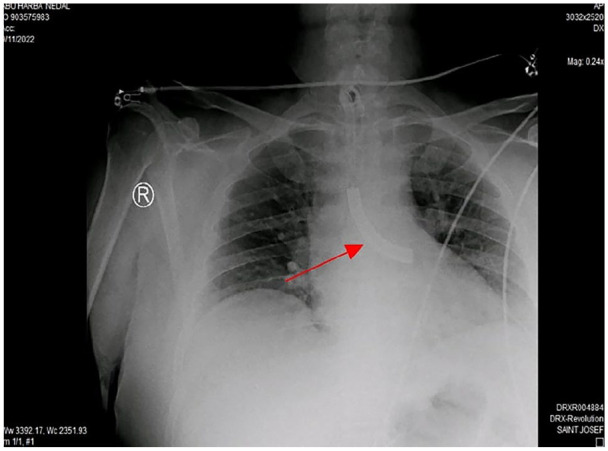

Case presentation: A 43-year-old male, with a tracheostomy tube in place for 8 years following a neck blast injury, presented with a foreign body in his airway. Chest X-ray revealed a fractured metallic tracheostomy tube lodged in the left main bronchus. The tube was successfully removed by rigid bronchoscopy under general anesthesia, and the patient was discharged in good condition with a new tracheostomy tube.

Discussion: Tracheostomy tubes, typically made of polyvinyl chloride or metal, can fracture due to prolonged use without regular check-ups, or replacement. Patients may present with mild respiratory symptoms or be asymptomatic. Diagnosis is confirmed by X-ray, and removal is performed via rigid bronchoscopy.